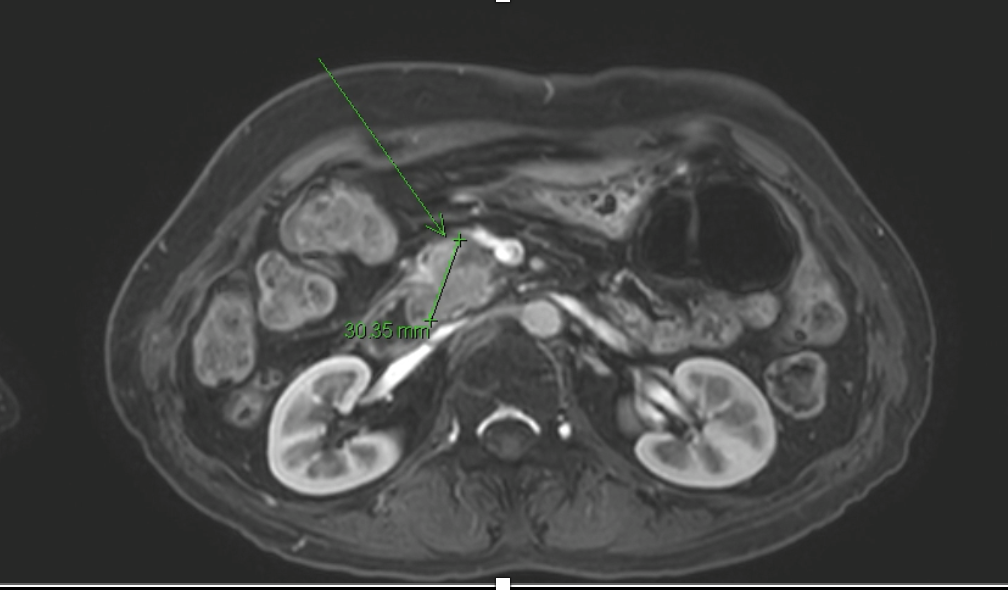

MRI

1. Multiphase CT and MRI

- MRI, particularly with MRCP and diffusion-weighted imaging, offers superior soft tissue contrast and is especially helpful in detecting is attenuating tumors. It also enables non-invasive visualization of the pancreatic duct and bile duct, making it highly valuable in evaluating ductal obstruction. Furthermore, MRI is preferred in patients with renal impairment or iodine contrast allergy and provides multiparametric data that can aid in tumor characterization and staging.